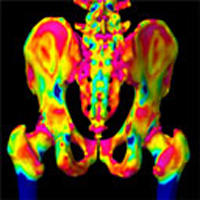

Метод, разработанный доктором Грэхэмом Трис (факультет инженерного дела) и доктором Кеном Пул (факультет медицины), использует изображения компьютерной томографии для точных измерений толщины кортикального слоя костей, - твердого внешнего слоя компактного вещества костной ткани, который окружает трабекулярную кость. Толщина кортикального слоя – ключ-индикатор, определяющий риск переломов.

На данный момент, основная технология, которая используется для определения риска переломов – тест на плотность костного минерала. Метод использует DEXA-сканирование (двуэнергетическую рентгеновскую абсорбциометрию), определяющее уровни минералов, содержащиеся в кости. Альтернативным способом является Мультидетекторная Компьютерная Томография, которая дает более точные изображения структуры кости в 3D режиме, что обеспечивает точные субмиллиметровые измерения.

Метод, разработанный докторами Трис и Пул, увеличивает точность размеров кортикальной кости, что помогает врачам-консультантам отмечать изменения толщины в динамике по времени, и обеспечивает точность показаний толщины до 0.3 мм.

Получены тысячи измерений кортикальных костей с использованием данных сканнера-томографа и математической модели сканирующего процесса. Составляются 3D карты толщины, с идентификацией опасных тонких зон. Получение нескольких последовательных изображений описывают изменения кортикальной костной ткани в динамике по времени по всем областям скелета. Таким образом, контролируется процесс лечения остеопороза.